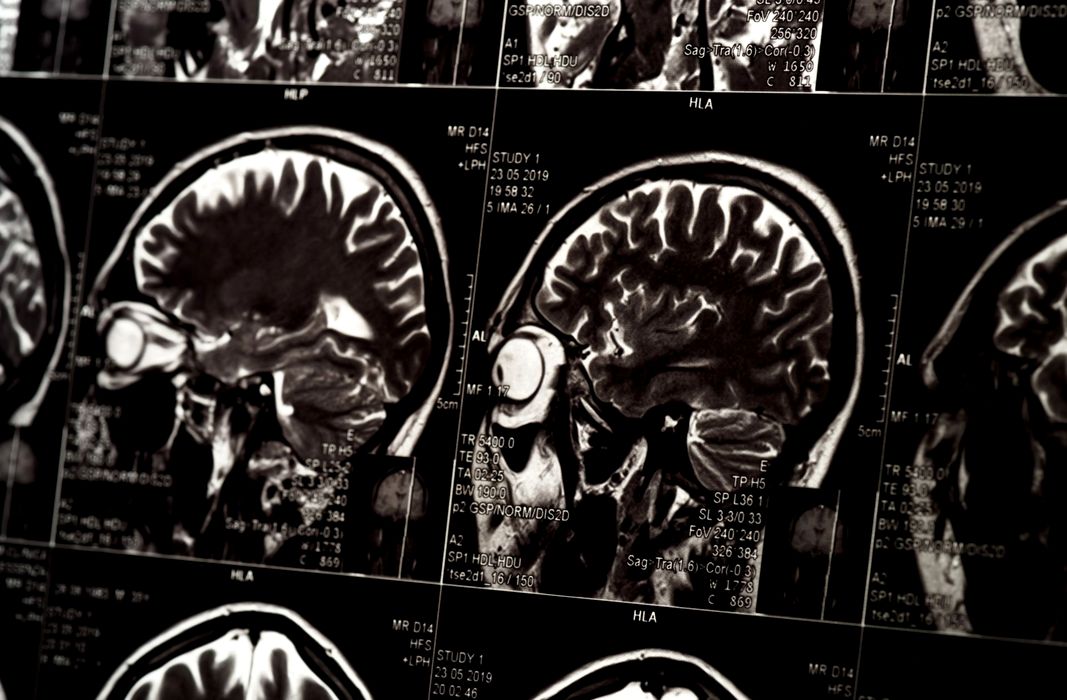

Creierul are un ritm ascuns care ar putea dezvălui inteligența

Creierul are un ritm ascuns care ar putea dezvălui inteligența. Cu cât ești mai inteligent, cu atât creierul tău este mai bine sincronizat cu propriul său ritm intern, arată un nou studiu. Creierul are un […]